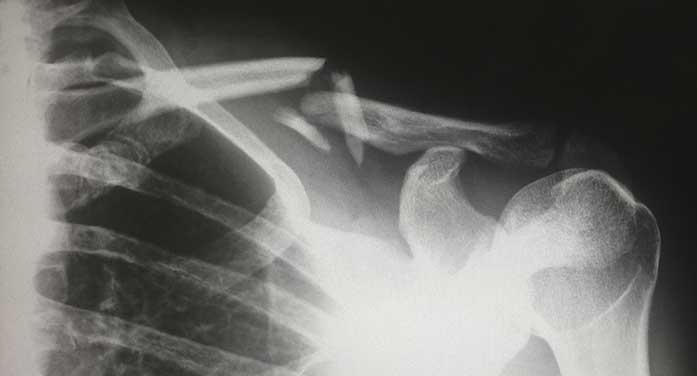

Disappointment doesn’t even begin to describe the feeling of being sidelined after a fluky fall off my bike on a secondary road south of Saskatoon in which I broke my collarbone and was unconscious for several minutes. Every day, I’m grateful I didn’t end up with a brain injury.

Life is all about adapting to surprises, good and bad. And after spending five hours in the emergency room getting a battery of tests, I left Royal University Hospital in Saskatoon with an arm sling and a plan. I’d fly to southern Ontario to stay with my mother, see my three sisters and heal up until I could rejoin the ride.